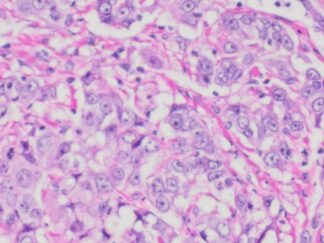

| SKU# | Organ | Pathology Diagnosis | Therapies (Chemotherapies ,radiation and Hormone) before Collection of Sample |

Gender/Age (year) | Tumor Area(%) | Tumor Grade | TMN/Stage | ER,PR & HER2 IHC Data |

| HuPS-02011T | Breast | Infiltrating duct carcinoma |

No | Female/30 | 25% | III | T2M0N2 | ER(85%+++), PR(65%+++), Her2(Score -3) |